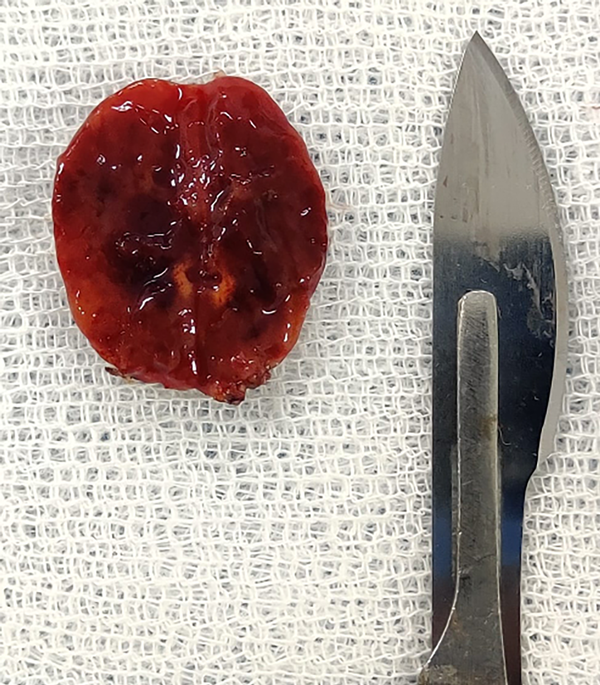

Fig 5. Caso 1. Pieza quirúrgica macroscópica de lesión vascular.

Posicionamos al paciente en decúbito prono con soporte dorso lumbar. Se utilizó cabezal de Mayfield para fijar la cabeza. Se realizó incisión lineal desde C2 a C5. Se disecó tejido hipodérmico hasta ligamento vertebral posterior; se abrió la fascia muscular hasta exponer las apófisis espinosas y las láminas. Se procedió a realizar laminectomía C3-C5 y flavectomía C2-C6. La duramadre fue abierta en forma lineal. Se realizó monitoreo neurofisiológico con onda D. Se visualizó lesión voluminosa que desplazaba raíces y cordón medular a derecha de color gris-rosada, vascularizada que impresionaba nacer de raíz sensitiva C4 izquierda. Se colocaron en ambas aferencias arteriales en el polo superior, clips transitorios por 5 minutos sin cambios neurofisiológicos, continuando con la sección de ambas aferentes. Se luxó la lesión que quedó pendiente de vena arrosariada en cara posterior de la médula, la cual se coaguló y seccionó con remoción de la lesión en bloque.